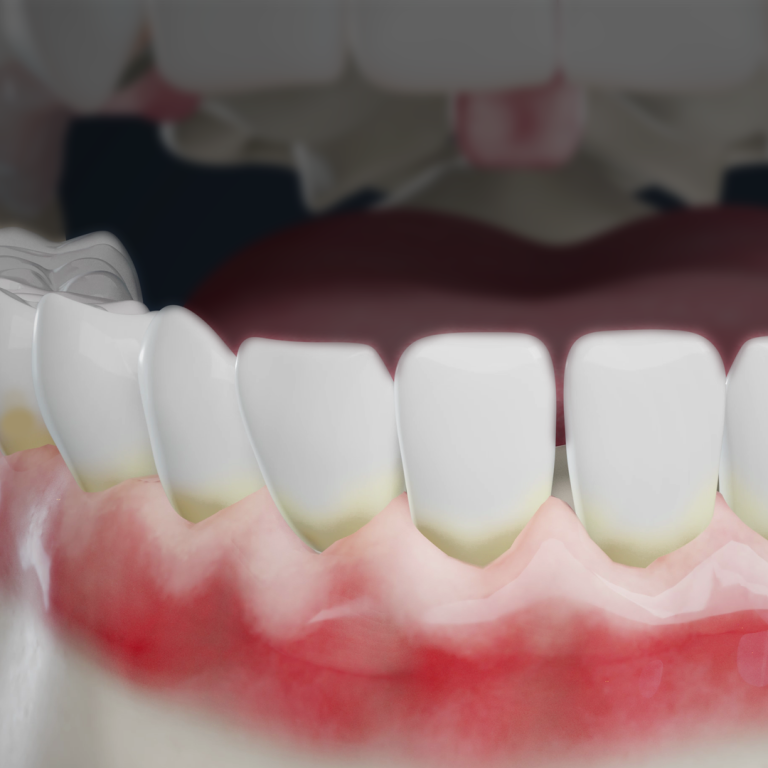

Teeth appear longer when gum recession exposes more of the tooth surface. This usually happens gradually and may be linked to gum disease, aggressive brushing, or teeth grinding.

Gum recession is one of the most common conditions we see in dentistry, and it often develops gradually and without pain. Many patients don’t recognize serious changes until they notice increased tooth sensitivity, change in color at the gumline, or their teeth appear longer than they used to.

Gum recession is not a diagnosis by itself, but a visible indicator that occurs when the gum tissue gradually pulls away from the tooth making teeth appear longer.

What’s important to understand is that healthy gums don’t shrink or move on their own, so gum recession is usually a sign of an underlying issue. In many patients, gum recession is the first visible warning sign that inflammation or bone loss may already be occurring beneath the surface.

Think of your gums like a protective seal. Healthy gum tissue forms a barrier around each tooth’s roots to protect underlying bone from bacteria, food debris, and excessive force. When that seal is strong, your teeth are supported, stable, and far less vulnerable to damage.

Exposed roots are significantly more prone to decay, sensitivity, and bone loss that will progress without proper treatment.